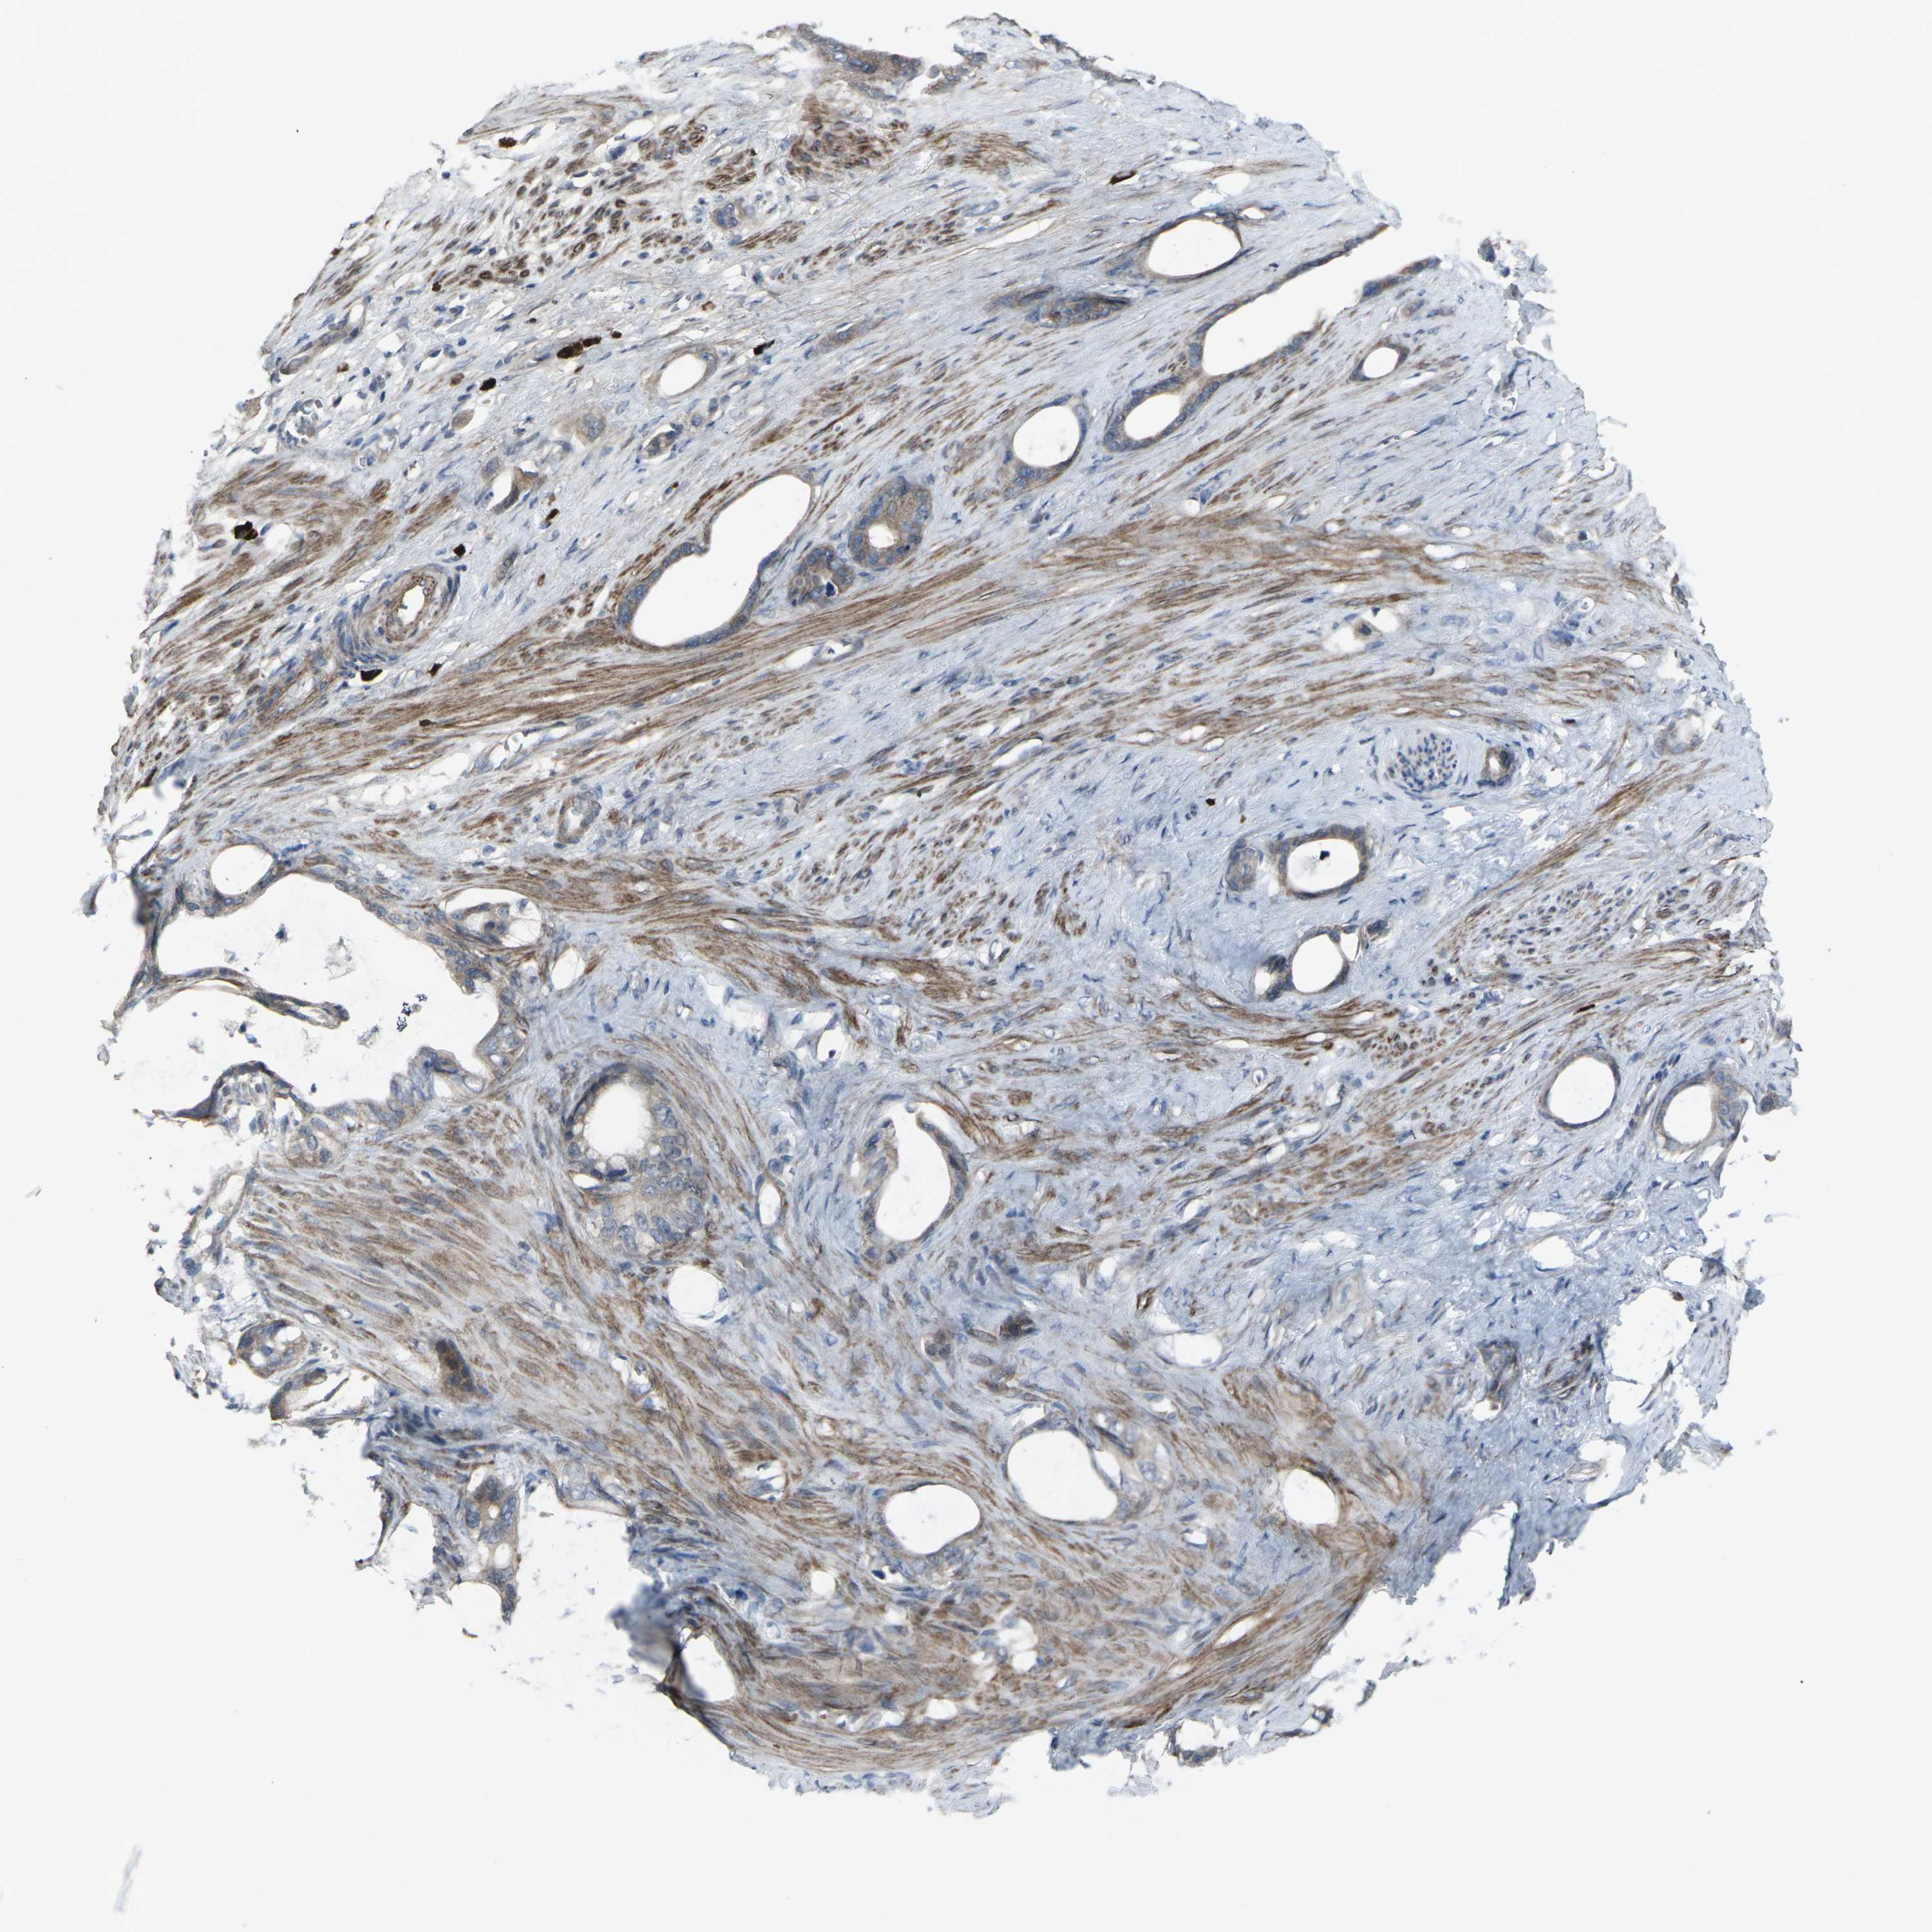

STOMACH CANCER - Protein expressioni

A mouse-over function shows sample information and annotation data. Click on an image to view it in a full screen mode. Samples can be filtered based on level of antibody staining by selecting one or several of the following categories: high, medium, low and not detected. The assay and annotation is described here.

Antibody stainingi

Antibody staining in the annotated cell types in the current human tissue is reported as not detected, low, medium, or high, based on conventional immunohistochemistry profiling in selected tissues. This score is based on the combination of the staining intensity and fraction of stained cells.

Each image is clickable and will lead to virtual microscopy that enables deeper exploration of all samples and also displays staining intensity scores, fraction scores and subcellular localization as well as patient and tissue information for each sample.

Antibody CAB011684

Staining

High

Medium

Low

Not detected

Intensity

Strong

Moderate

Weak

Negative

Quantity

>75%

75%-25%

<25%

None

Location

Nuclear

Cytoplasmic/membranous

Cytoplasmic/membranous,nuclear

Adenocarcinoma, NOS

Adenocarcinoma, High grade